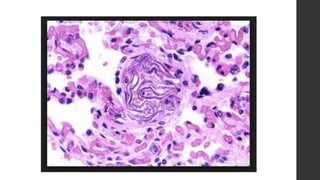

• Renal glomeruli:

fibrin thrombi is usually found in capillary lumens

• Renal glomeruli: fibrinthrombi is usually found in capillary lumens (indicating DIC as a part of AFES)